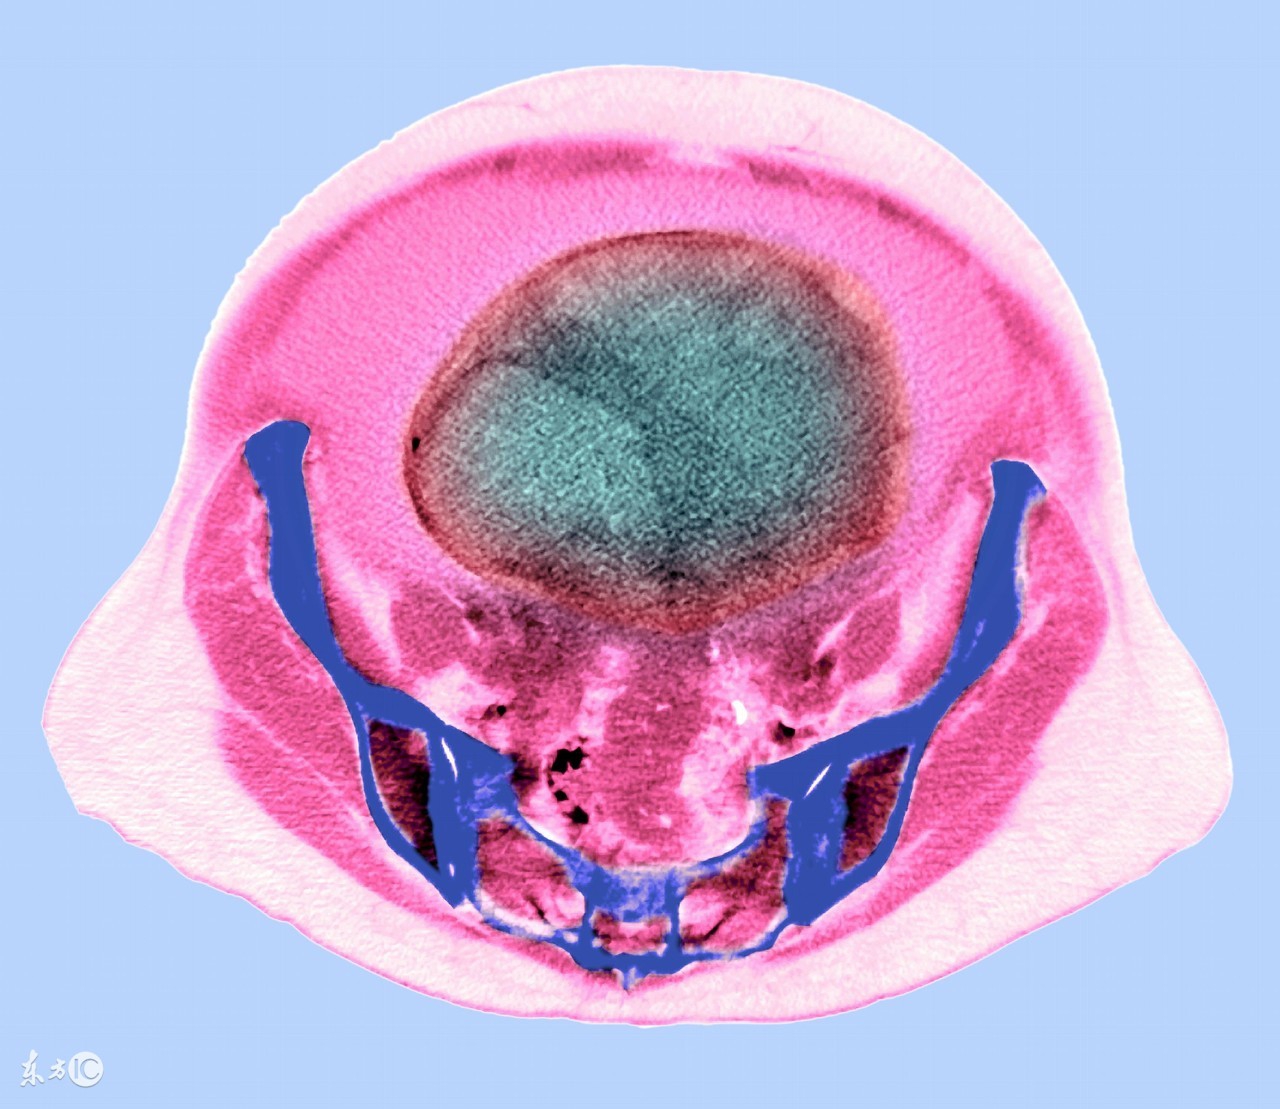

卵巢癌是发生于卵巢组织的恶性肿瘤。临床上可出现下腹不适、腹痛、腹部肿块、月经紊乱、压迫等症状。卵巢癌有起病隐匿,早期不易发现,易转移,预后差等特点。卵巢癌严重者随时都有生命危险,所以为了使卵巢癌带给患者的危害降到最低,患者除了积极配合医生的治疗外,还要学会自我保健。